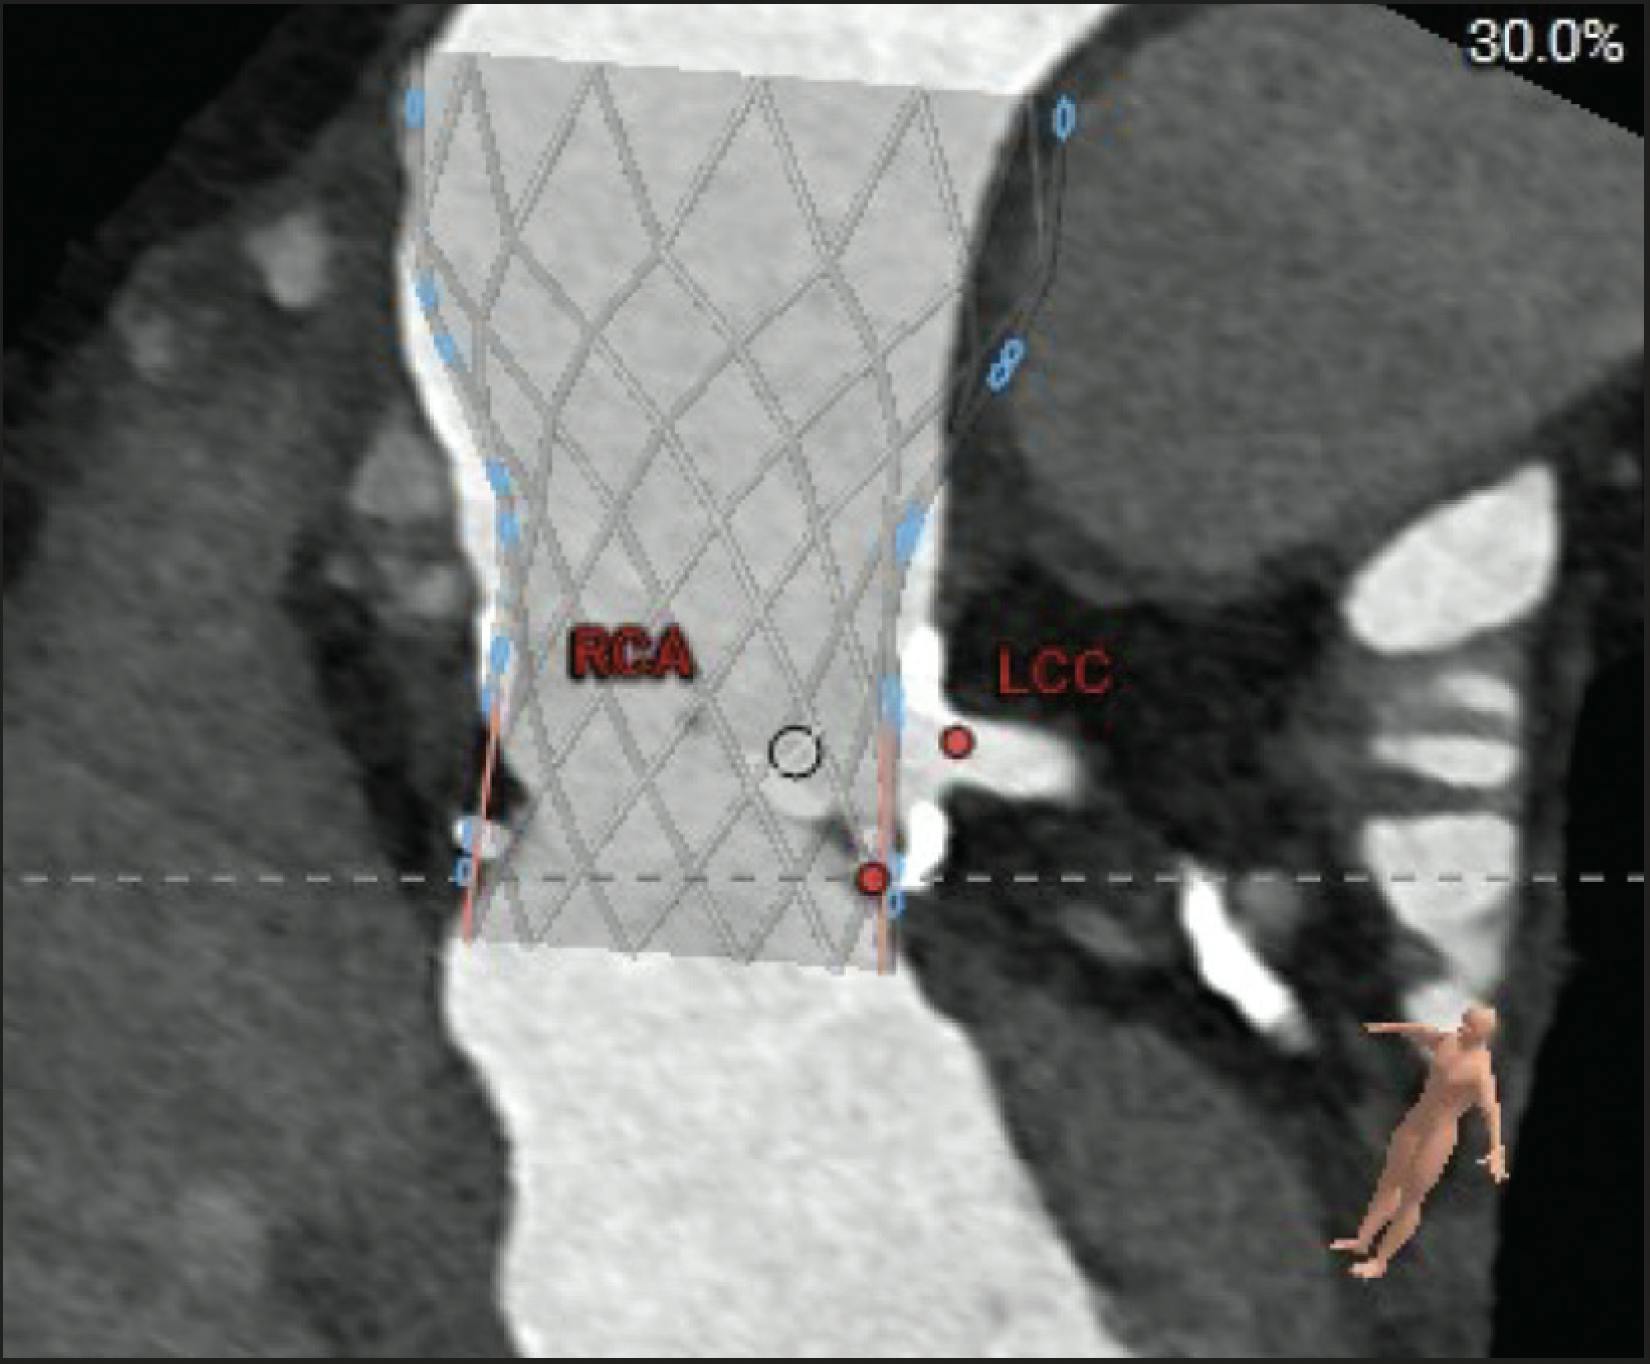

Given the small true internal diameter (approximately 19 mm per Valve-in-Valve app) and the fact that the Trifecta valve is not amenable to valve fracture, there was concern for impaired hemodynamics. Although a supra-annular self-expanding valve was considered, the tall skirt height raised concern for coronary obstruction due to the neoskirt plane (Figure 3). Therefore, a balloon-expandable valve with a shorter skirt was selected. The patient’s body surface area was 1.53 m2. To mitigate coronary obstruction risk, we planned sequential “doppio” balloon-assisted BASILICA (BA-BASILICA) of the left and right cusps followed by TAVR using a balloon-expandable prosthesis.

Figure 3. CT analysis: risk of skirt coronary obstruction from the skirt.